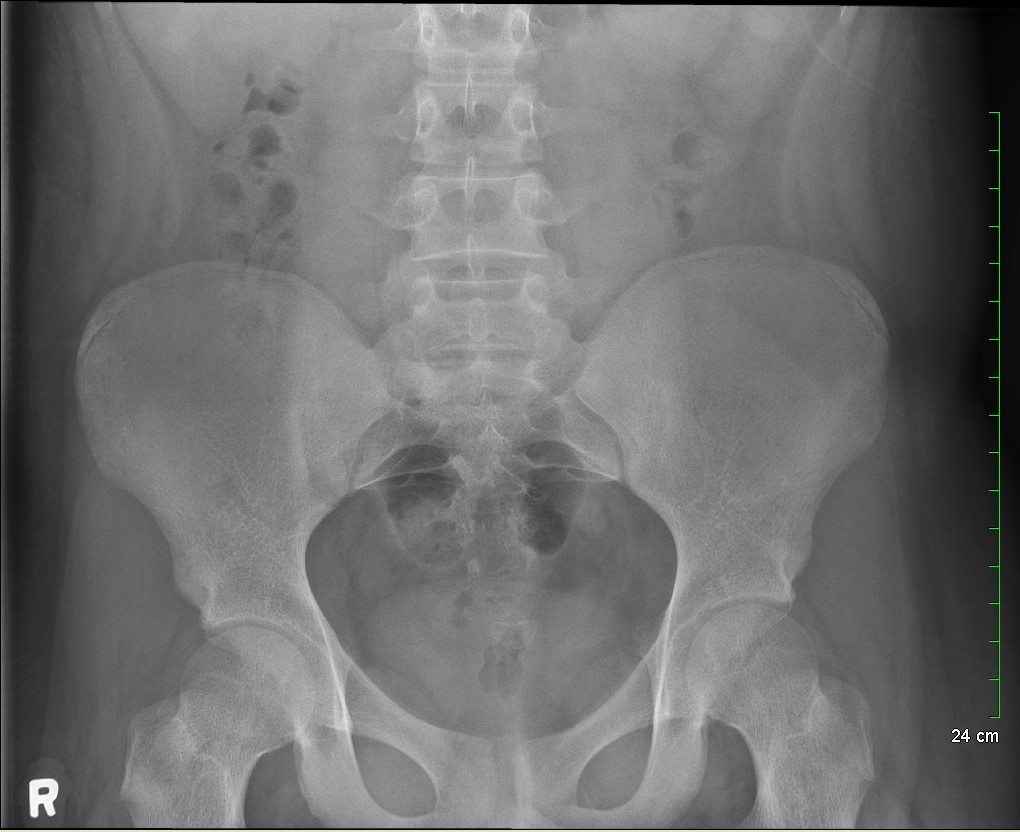

Because the patient presented with prolonged vomiting, a complete blood count (CBC), comprehensive metabolic panel (CMP), lipase, and kidney, ureter and bladder (KUB) was obtained. Initial labs showed only mild transaminitis and metabolic acidosis (AST 106, ALT 188, HCO3 15). KUB revealed the following images:

Subsequent workup

KUB read as normal by radiology. However, because of the enlarged heart border found incidentally on KUB, troponin I (0.05 ng/mL), B-type natriuretic peptide (BNP) (2186 pg/mL), and chest x-ray (CXR) was obtained, which showed the following: